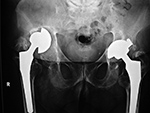

Osteolysis and particle disease in right hip implant

There is displacement of the right acetabular implant component and osteolysis from granulomatous particle disease. A left metal upon metal hip implant is present.